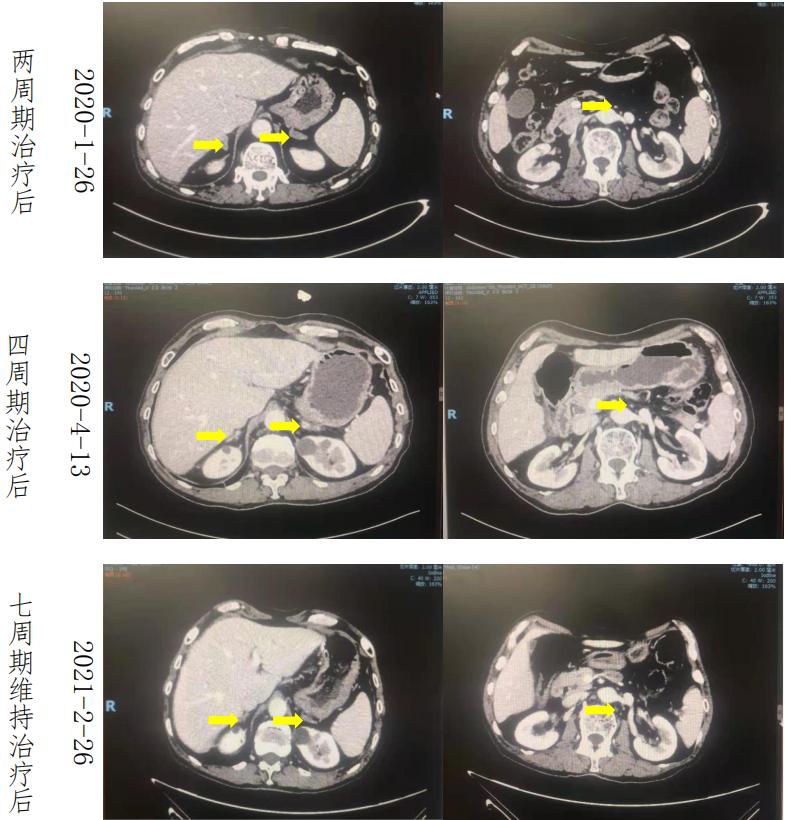

疗效评价 :二线化疗联合免疫(伊立替康+卡瑞丽珠单抗)治疗 4 周期后肾 上腺及腹膜后病灶明显缩小,联合方案治疗 6 周期后疗效评价(PR),后续予以卡瑞丽珠单抗维持治疗,维持治疗期间肿瘤未出现增大,末次治疗后疗效评价 (PR)。目前患者二线治疗的 PFS 达到 14 个月。

肿瘤标记物:化疗联合免疫治疗 2 周期后标记物显著下降,4 周期后标记物降至 正常范围并维持至今。